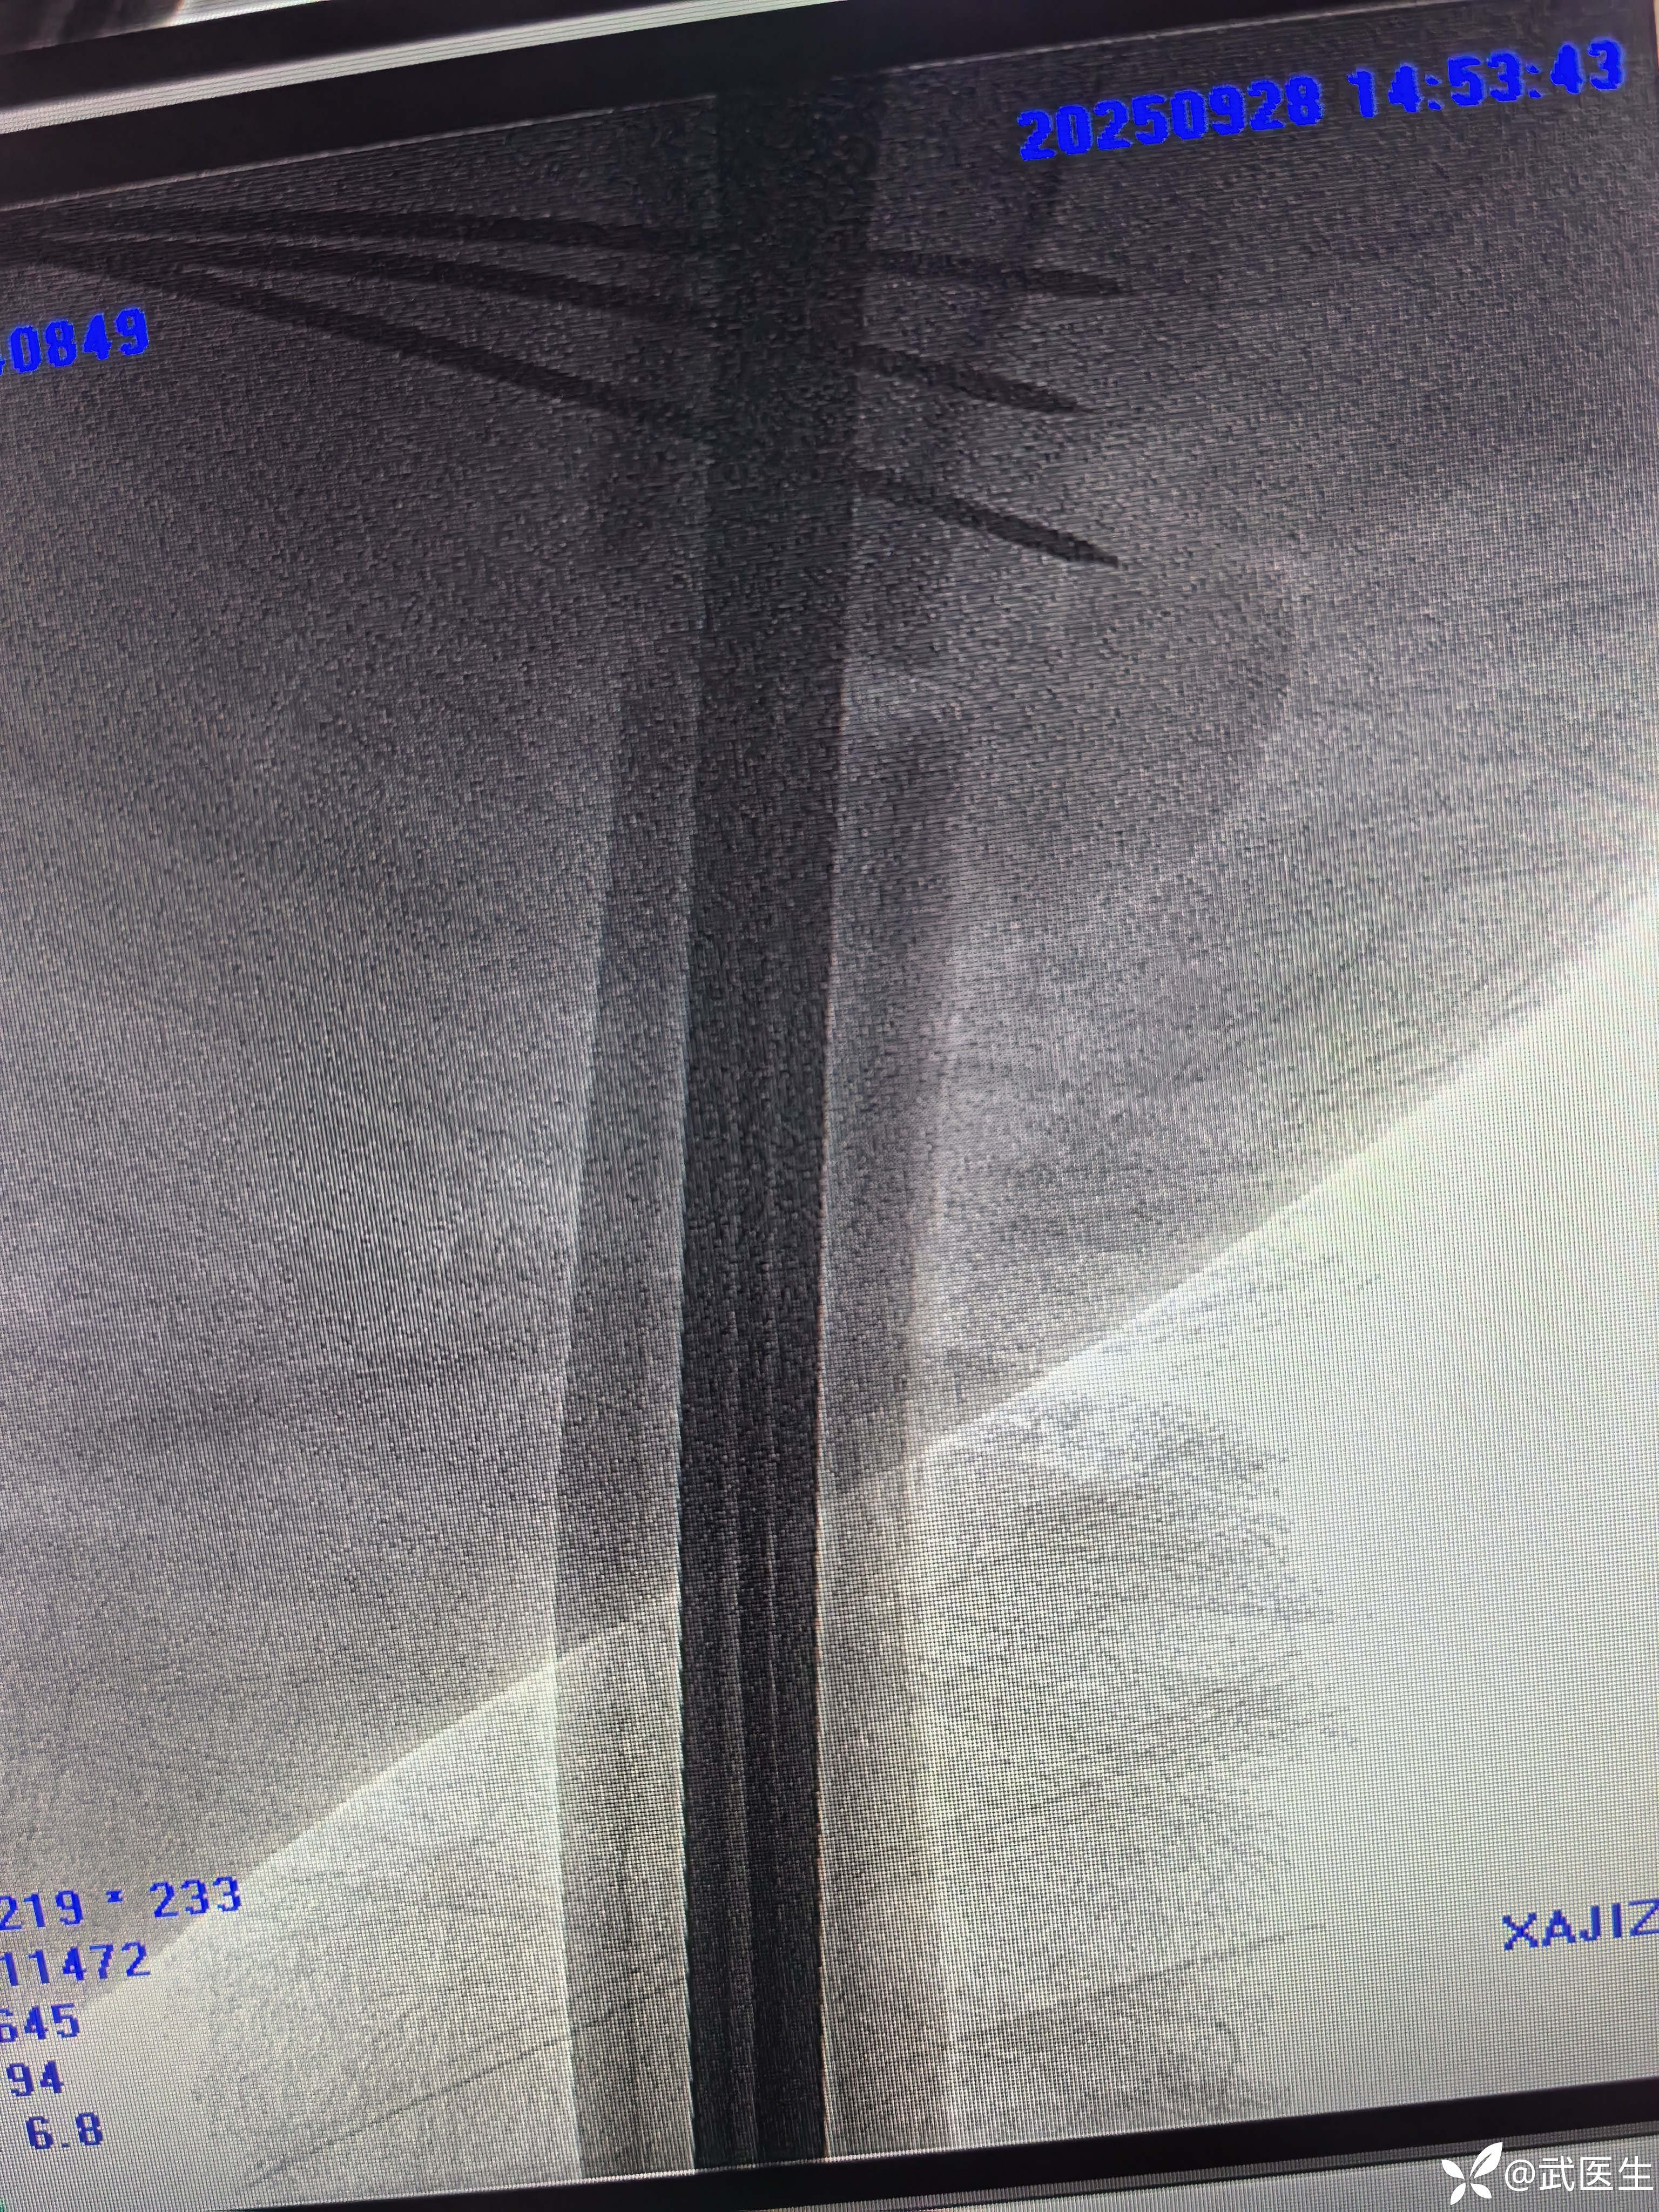

常规侧卧位,定位

合适入针点,开口,对位差,手法复位

利用金手指置入导针,扩髓,步骤省略